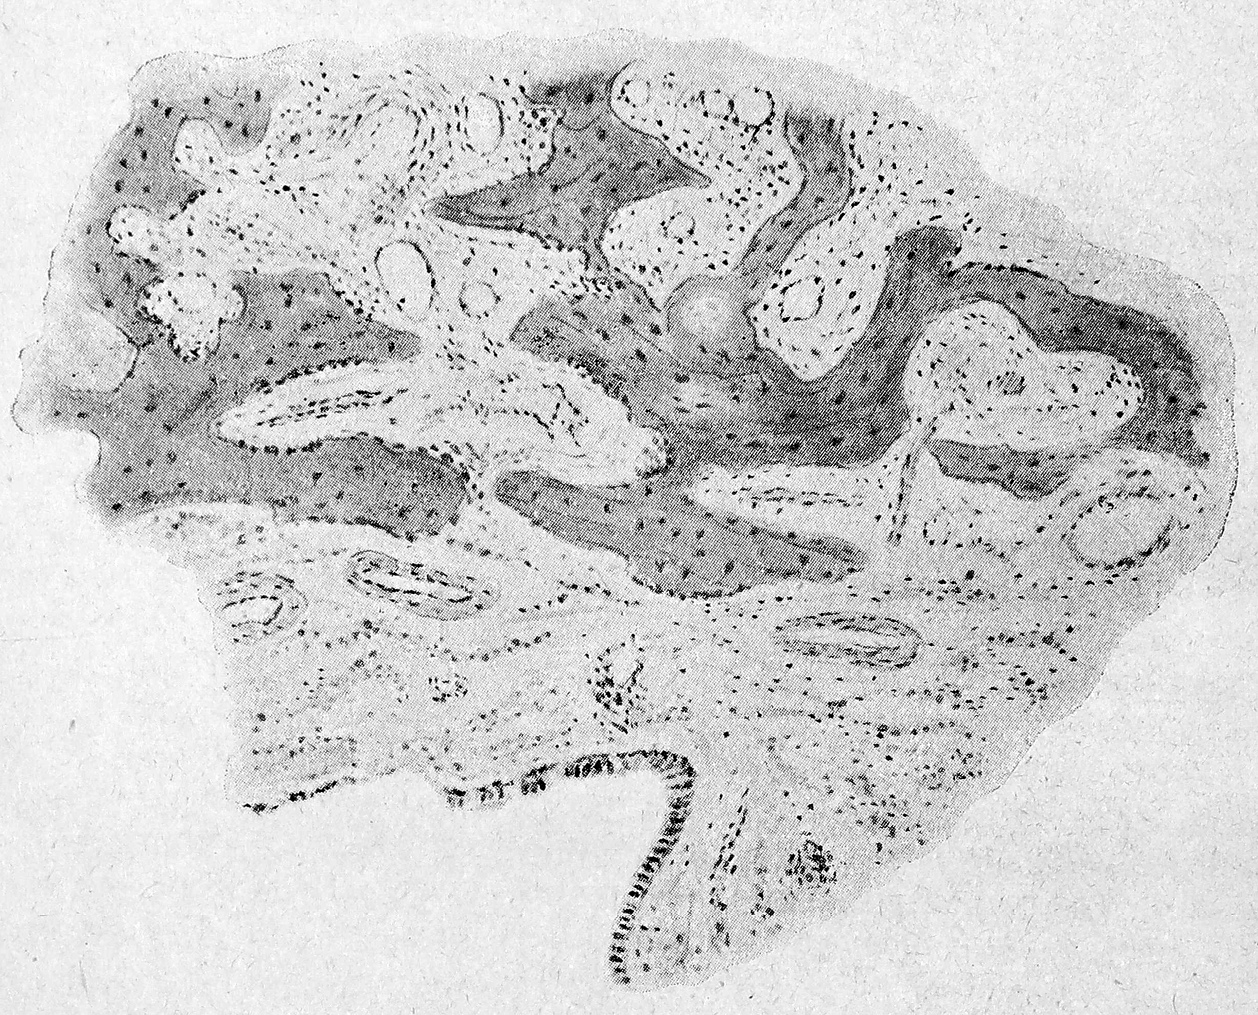

Микроскопическое исследование показало (рис. 4), что на внутренней поверхности полости находится слой фибрина, в петлях которого заложены круглые клетки. Далее видны расширенные сосуды, фибробласты в небольшом количестве, большое скопление круглых клеток, слой мелкоклеточковой инфильтрации, лимфоциты, полиморфноядерные лейкоциты, плазматические клетки. Ни эпителия, ни желез ни в одном из препаратов не обнаружено. Следующий слой—новообразованная, волокнистая соединительная ткань. Далее лежит более плотная соединительная ткань, за слоем которой—костная ткань в состоянии резорбции. Еще более кнаружи обнаружены, участки кости с ясно выраженными костными перекладинами и костным тельцами, сослоем остеобластов по периферии.

Рис. 4 Участок из поперечного среза станки кистовидно расширенной High m отовой полости. Слой фибрина, в петлях которого встречаются круглые клетки (полиморфноядерные лейкоциты). Глубже—слой мелкоклеточковой инфильтрации с расширенными сосудами, наполненными красными кровяными тельцами и слой соединительной ткани. Эпителий и железы отсутствуют.